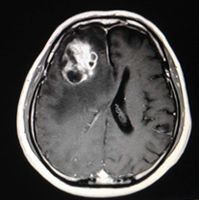

くも膜下出血

くも膜下出血の例です。頭痛で発症しましたがすぐには医療機関を受診せず数日経過してからの診断となりました。出血量が少なくまた再出血がなかったために血管内手術で完治することができました。突然の頭痛の場合にはすぐに医療機関を受診して診断を受けることが大切です。